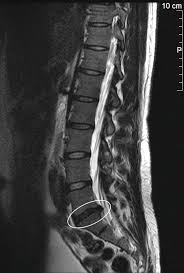

En demasiadas ocasiones, las imágenes que se utilizan para diagnóstico sirven como referencia para encontrar un “culpable” del dolor en la espalda. Se ha escrito ya varias veces sobre la poca correlación entre el dolor y la imagen, ateniéndose a la cantidad de alteraciones como degeneración discal, hipertrofia facetaría o protrusiones discales entre otras, que cursan de forma asintomática en todo tipo de pacientes.

Un estudio que revisaba sistemáticamente artículos anteriores llevado a cabo en 2015 (1), analizaba datos recogidos sobre la prevalencia de hallazgos en individuos asintomáticos, seleccionando grupos por décadas de edad. 20, 30, 40 50, 60, 70 y 80 años y posteriormente determinaban la prevalencia estimada para cada una de las edades. Se analizaron un total de 3110 individuos asintomáticos y por ejemplo, la degeneración discal se apreciaba hasta en un 37% de pacientes veinteañeros, y se incrementaba hasta un 96 % en el grupo octogenario. Los abultamientos discales aumentaban desde un 30% a los 20 a un 84% a los 80 y las protusiones desde un 29% en gente de veinte a un 43% en gente de 80.

Esto son sólo algunos de los ejemplos que evidencian que los hallazgos en imagen a medida que avanza la edad deberían de ser menos fiables y por lo tanto, no debemos ser conformistas, hemos de interpretar el contexto de cada paciente en concordancia con su condición clínica.

Debemos concluir por lo tanto que la mayoría de los cambios que se producen en la espalda son proceso normales relacionados con la edad, y no tanto una lesión o proceso patológico.

Se debería por lo tanto, incluir en muchas de las pruebas diagnósticas por imagen como podrían ser las resonancias magnéticas, Rx o los TAC, porcentajes y referencias al paciente para así informarse de casos como el suyo que se presentan de forma asintomática y poder interpretar mejor sus “fotos”